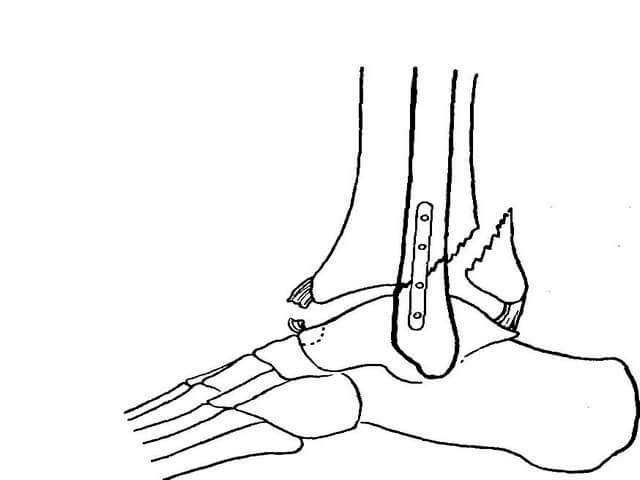

Хирургическое вмешательство

Операции выполняют при:

- переломах обеих лодыжек;

- открытых переломах;

- сложных травмах;

- разломе больше- и малоберцовой кости более чем на треть;

- сложных разрывах связок;

- застарелых переломах.

Тип операции зависит от характера повреждения. Хирург может:

- скреплять межберцовое соединение, если имели место переломы медиальной лодыжки и малоберцовой кости. В таком случае через мало- и большеберцовую кость фиксируется болт под углом от латеральной лодыжки. С помощью сверла делают каналы для введения приспособлений.

- Выполнять остеосинтез медиальной лодыжки, если диагностированы супинационные переломы. В таком случае под прямым углом вводится двухлопастной гвоздь, фиксирующий медиальную лодыжку. Латеральная закрепляется штифтом, а отломки – винтами.

- Выполнять остеосинтез латеральной лодыжки при пронационных переломах. В таких случаях вдоль оси малоберцовой кости через латеральную лодыжку проводят штифт, а медиальную фиксируют гвоздем.

- Выполнять остеосинтез фрагментов большеберцовой кости, если имеются ее переломы по заднему отделу нижнего конца. Для скрепления используют длинный шуруп.

Впоследствии на конечность накладывают гипс таким образом, чтобы оставить доступ к ране. По окончании операции и во время реабилитации качество сращения костей контролируют посредством проведения рентгенографии.